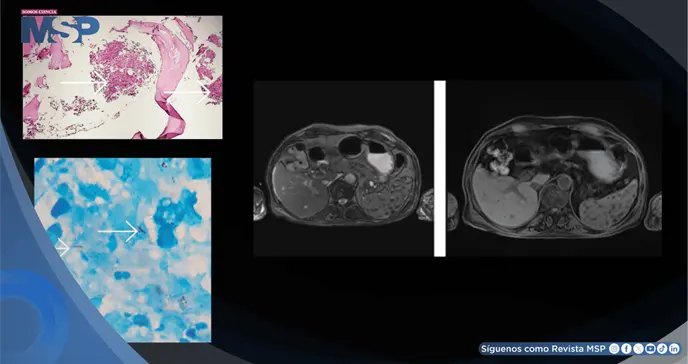

La resonancia magnética abdominal posterior describió múltiples lesiones pequeñas en el hígado y el bazo, sugestivas de microabscesos, junto con esplenomegalia. Los cultivos microbiológicos habituales, no obstante, seguían siendo negativos.

Ante la persistencia de la citopenia, se procedió a realizar una aspiración y biopsia de médula ósea. Si bien la citometría de flujo fue normal, el examen histopatológico fue revelador: mostró una respuesta granulomatosa con caseificación.

La tinción para bacilos ácido-alcohol resistentes (BAAR) fue positiva, confirmando la presencia de micobacterias. Este hallazgo estableció el diagnóstico definitivo de tuberculosis extrapulmonar con afectación de la médula ósea.

La biopsia de médula ósea que muestra granulomas caseosos, corroborada por una tinción de BAAR positiva, sigue siendo el estándar de oro para el diagnóstico. Los hallazgos de imagen, como microabscesos hepáticos y esplenomegalia, brindan un apoyo adicional valioso, especialmente en pacientes inmunocomprometidos.